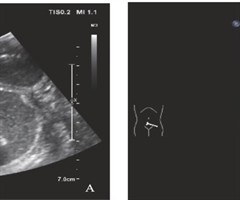

经直肠超声造影对肠腔狭窄型直肠癌的诊断价值

摘要:目的:评估经直肠超声造影(CEUS)对肿瘤所致肠腔狭窄型直肠癌的诊断价值。方法对49 例确诊为直肠癌患者术前行经直肠CEUS 和磁共振成像(MRI)检查,以直肠癌根治术术中肿瘤定位及术后病理结果为金标准,比较两种检查方法对直肠癌病变的...